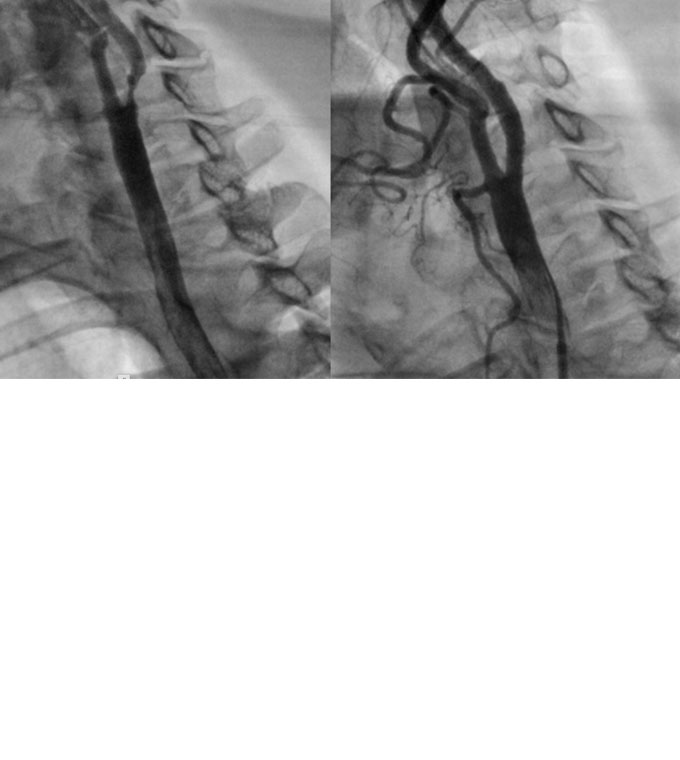

Als Alternative zur Operation an den Halsgefäßen hat sich in den letzten Jahren die Implantation von Stents in dieser Gefäßprovinz etabliert.

Mit diesem Verfahren bieten wir in unserem Behandlungsschwerpunkt eine hohe Sicherheit.

Links: Hochgradige Engstelle der Halsschlagader vor der Intervention. Rechts: Resultat an der Halsschlagader nach Implantation einer Gefäßstütze (CAS). Die Engstelle wurde komplett beseitigt